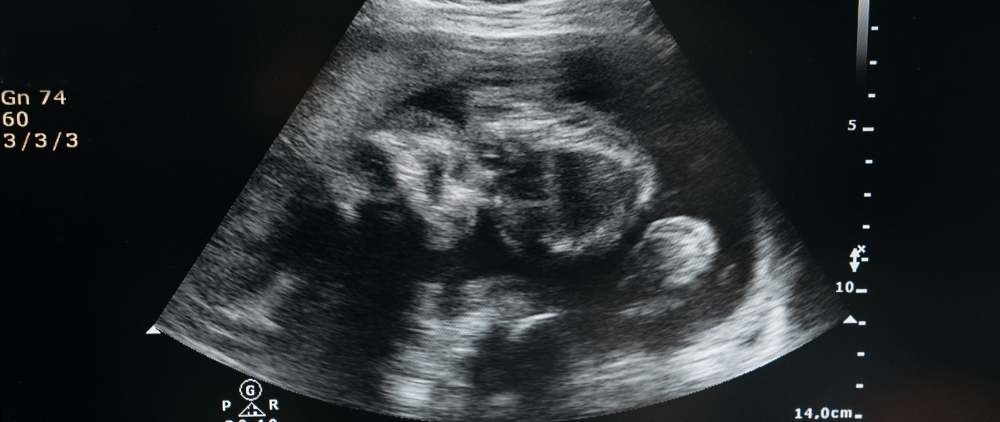

Earlier this month, we shared the positive news that the Department of Health and Human Services (HHS), in conjunction with the Food and Drug Administration (FDA), was initiating a review of the abortion drug mifepristone, the first pill in a two-drug regimen used to terminate first-trimester pregnancies. The investigation was launched in response to dozens of public officials drawing attention to a recent study that the drug is 22x more dangerous than the FDA currently claims. Conservatives viewed the investigation as heralding the onset of pro-life policies from HHS and FDA – but unfortunately, recent actions have proved that to be a false hope.